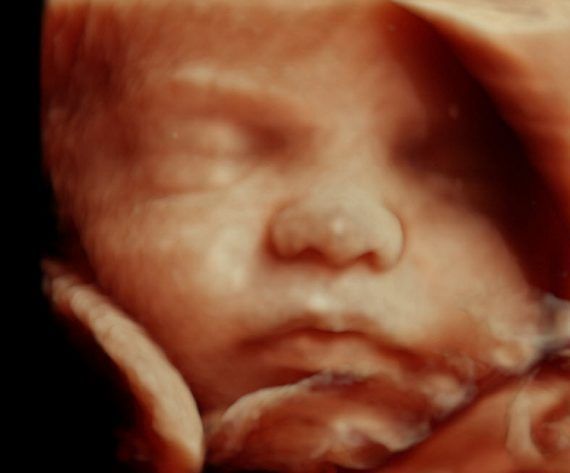

«Όταν είδα αυτή την εικόνα, που δεν ήταν επίπεδη όπως τα προηγούμενα υπερηχογραφήματα, ούτε ασπρόμαυρη, αλλά μια ρεαλιστική απεικόνιση του παιδιού μου, ένιωσα τι σήμαινε πραγματικά το ότι είμαι έγκυος», είπε.

Οι γνωστοί υπέρηχοι με απεικόνιση 3D θα γίνουν σύντομα παρελθόν σε κάθε κλινική και νοσοκομείο, αφού η τεχνολογία 4D υπερήχων, όχι μόνο απεικονίζει ρεαλιστικά το μωρό, αλλά επιτρέπει να δεις ακόμα και τις εκφράσεις του προσώπου του, ακόμα και το χασμουρητό του.

Η τεχνολογία των HD υπερήχων μπορεί να χρησιμοποιηθεί από το πρώτο τρίμηνο της εγκυμοσύνης και επιτρέπει στους γιατρούς να έχουν μια καλύτερη εκτίμηση της ανάπτυξης του μωρού, ενώ δίνει στους γονείς μια λεπτομερή εικόνα του παιδιού, πολύ πριν γεννηθεί.

«Το HD δείχνει καθαρά το πρόσωπο, αλλά και τον τόνο του δέρματος του εμβρύου» λέει ο Δρ. Bernard Benoit, ο επικεφαλής του τμήματος υπερήχων στη Μαιευτική κλινική του Νοσοκομείου «Princess Grace» στο Μονακό. «…Μπορούμε να αλλάξουμε το φωτισμό της εικόνας μας και να δούμε ξεκάθαρα τα χείλη, τη μύτη, ως και τα βλέφαρα του μωρού.

Αν έχει κάποια δυσμορφία, η εικόνα βοηθά τους γονείς να προετοιμαστούν για τη ζωή τους μαζί του. Το να βλέπουν ξεκάθαρα από νωρίς το παιδί, δημιουργεί δεσμό μαζί του, πολύ νωρίτερα από τη γέννηση.

Αρκετοί γονείς μάλιστα, καταλαβαίνουν από την εικόνα σε ποιον μοιάζει».

Μόλις η Elisabeth, μια έγκυος γυναίκα από τη Μασαχουσέτη είδε το γιο της για πρώτη φορά μέσω των HD υπερήχων, ένιωσε τεράστια έκπληξη.